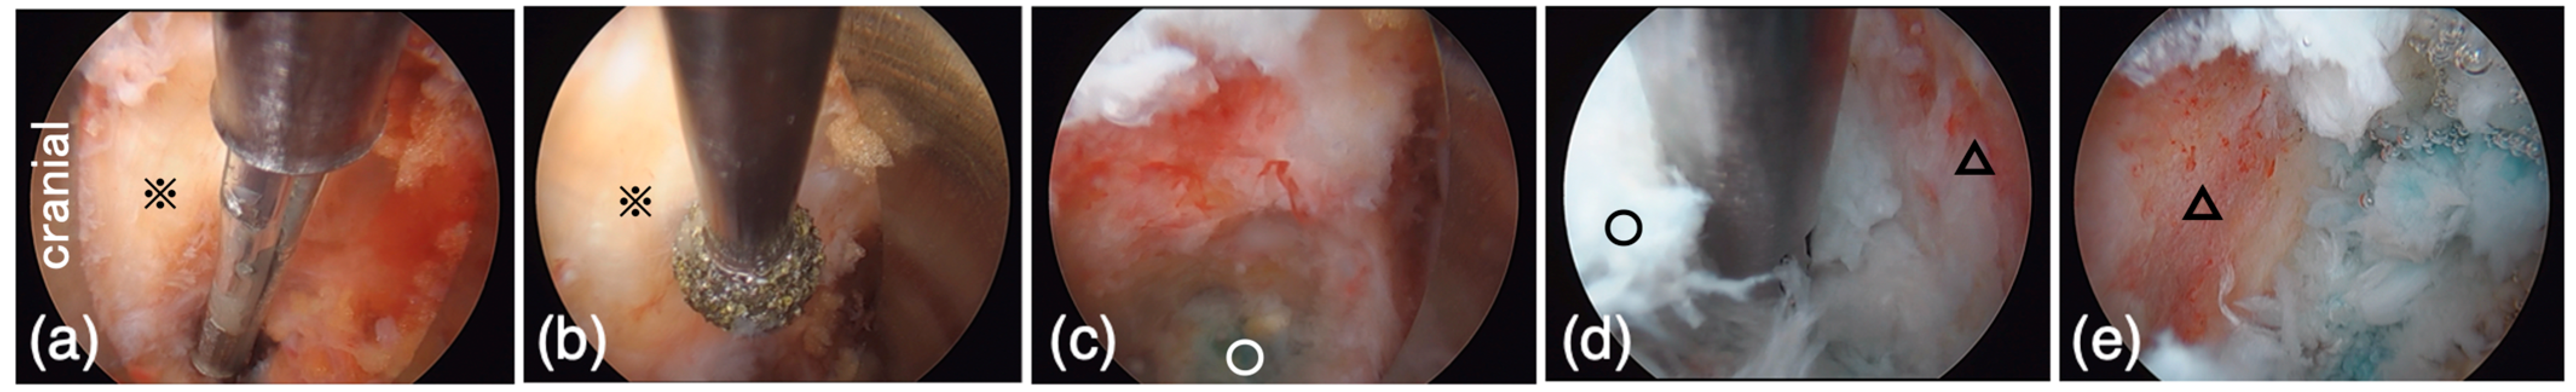

Figure 4.

In endoscopic view during the expansion of intervertebral foramen. The left side is cranial in all figures. (a) The lateral aspect of the facet joint (※) was exposed after the removal of soft tissue using forceps and a bipolar probe. (b) The ventral part of the foramen (※) was drilled using a high-speed burr. (c) The blue-stained intervertebral disc (○) was observed after the expansion of the foramen. (d) The disc (○) curettage was performed. The bony endplate (△) at the caudal vertebrate was exposed. (e) Also, the bony endplate (△) at the cranial vertebrate was exposed.